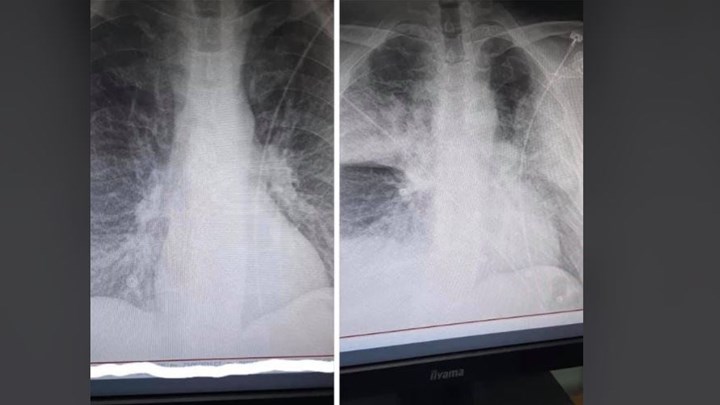

Ο κ. Μάνος Καρράς εξηγεί πως οι δύο ακτινογραφίες έχουν διαφορά 7,5 ωρών η μια από την άλλη. Πρόκειται για έναν 38χρονο ο οποίος είναι καπνιστής και διαβητικός. Ο ασθενής όπως αναφέρει είναι πλέον με μάσκα οξυγόνου.

Σύμφωνα με τον ίδιο, η πρώτη ακτινογραφία ήταν από την εισαγωγή στις 12 το μεσημέρι με 98% κορεσμό οξυγόνου και η δεύτερη, η επαναληπτική, πραγματοποιήθηκε στις 19:30 με τον ασθενή να είναι πλέον με μάσκα οξυγόνου. Όπως εξηγεί σε σχόλιο στην ανάρτησή του ο κ. Καρράς, τα «σύννεφα» στη δεύτερη ακτινογραφία συνήθως σημαίνουν υγρό οίδημα φλεγμονή και «είναι κομμάτι του πνεύμονα που “δεν αναπνέει”».

Λίγες ώρες αργότερα ο ακτινολογός κατέβασε την ανάρτησή του, καθώς αρκετοί χρήστες των social media παρατήρησαν πως στο κάτω μέρος της πρώτης ακτινογραφίας αναγράφεται η ημερομηνία “2015”.